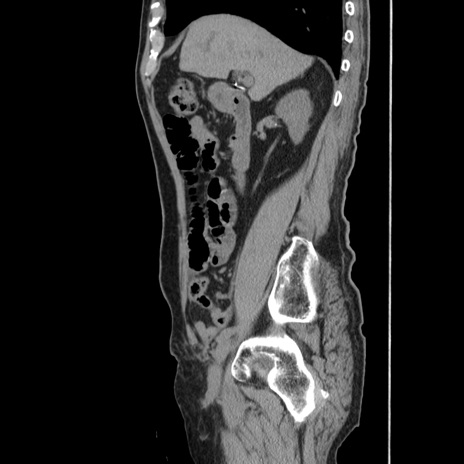

横断像

冠状断像